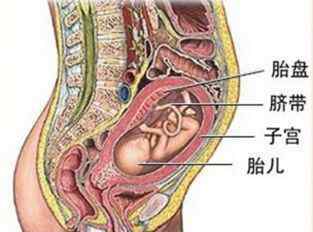

PS:胎儿在子宫内的位置在孕早期和孕中期变化较大。孕晚期由于胎儿体积增大,活动范围受限,胎位相对固定。此时,评估胎位具有重要意义。

正常胎位只有一个,就是枕位(头位的一种),即胎儿宝面向前(靠近母亲腹部),胸部面向后(靠近母亲脊柱),双手交叉放在胸前,双腿弯曲,头部弯曲,枕部(头顶)最低。

臀位是指婴儿头朝上,臀部朝下的位置。也可分为混合臀位、单臀位、单脚位、双脚位等几种情况。在胎儿位置不正的情况下,臀位是最常见的。

横卧是指胎儿卧于子宫腔内,垂直于母亲,分娩时先露手或肩的情况。横位也是最危险的胎位。